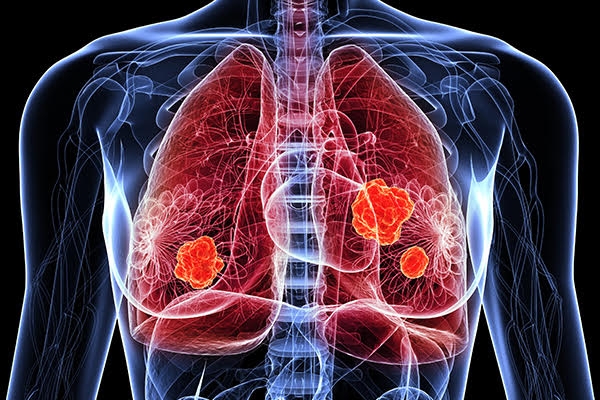

폐암은 폐에 비정상적인 암세포가 증식하여 덩어리를 형성하고 인체에 해를 미치는 것을 말합니다. 즉 폐에 생긴 악성종양을 말하며 폐 자체에 암이 발생하거나 다른 장기에서 생긴 암이 폐로 전이되어 발생합니다.

폐암 발병률과 폐암 사망률은 지속적으로 증가하고 있으며 폐암 진단을 받고 5년 이내 사망률은 86%나 된다고 합니다. 폐암은 재발이나 전이가 많고 완치율이 낮은 암입니다. 다른 암에 비해 사망률이 높습니다.